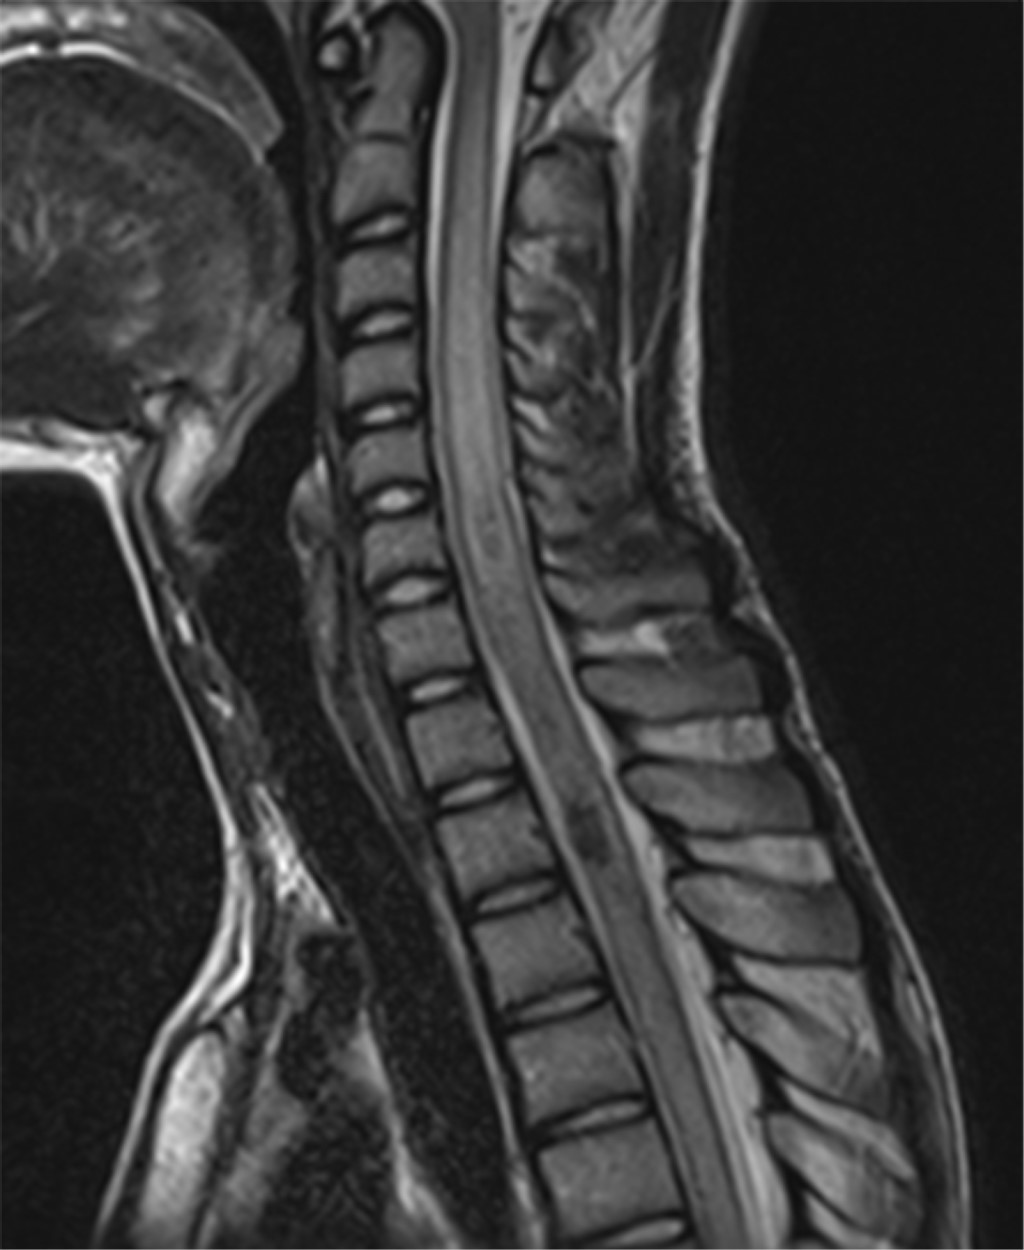

Se realizó resonancia magnética de eje neural con un ensanchamiento del cordón medular en la médula espinal desde C2 hasta T10, acompañado de evidencia de edema intramedular. Asociado a imágenes de susceptibilidad magnética en el nivel de T2-T3 (Figura 1), las cuales mostraron realce tras la administración de medio de contraste sugerentes de posibles vasos sanguíneos extradurales sin reforzamiento.

Figura 1